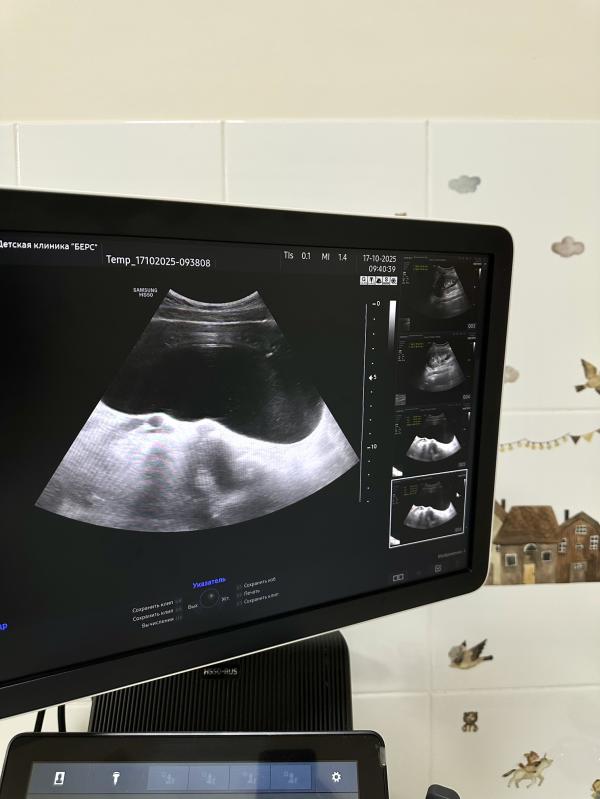

Во время осмотра врач обратил внимание на тревожащие симптомы и направил мальчика на общий анализ крови и мочи, а также УЗИ почек. Результаты обследования показали выраженное расширение лоханки, чашечек и мочеточника правой почки. Дополнительно выявили большое количество мочи в мочевом пузыре (объём мочевого пузыря составил целых! 700 мл) - хотя мальчик совсем не хотел идти в туалет.

Первый снимок демонстрирует расширенную ЧЛС поражённой почки, второй показывает сильно наполненный мочевой пузырь, а третий служит примером нормальной здоровой почки для наглядного сравнения.